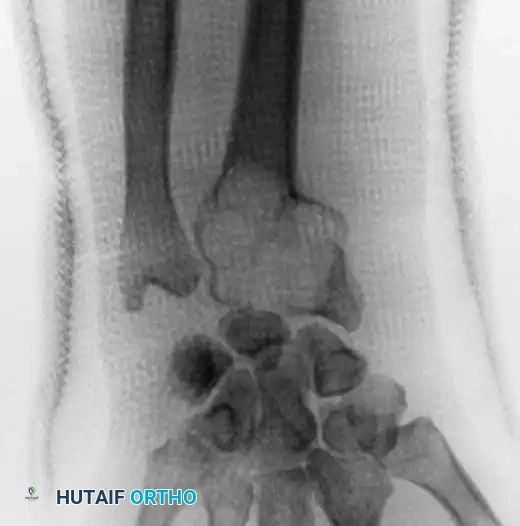

Plain Radiography

On plain radiographs, chondroblastoma typically appears as a well-circumscribed, eccentrically or centrally located lytic lesion confined to the epiphysis or apophysis. A defining feature is the presence of a surrounding rim of reactive sclerotic bone. Intralesional calcification—often described as a stippled or "fluffy" chondroid matrix—is visible on plain films in 30% to 50% of cases.

In skeletally immature patients, a well-circumscribed epiphyseal lesion that crosses an open physis (growth plate) into the metaphysis is virtually diagnostic of chondroblastoma.

In cases involving the distal radius (a common site for aggressive epiphyseal tumors like GCT), en bloc resection of the distal radius is performed. The tumor is excised with wide margins, sacrificing the radiocarpal joint.

To reconstruct the defect and restore forearm length, a structural autograft is harvested. The contralateral proximal fibula is an excellent anatomical match for the distal radius.

The fibular autograft is contoured and impacted into the medullary canal of the remaining radial diaphysis. A rigid wrist fusion plate is then applied dorsally, spanning from the radial shaft, across the fibular graft, and securing to the carpal bones (typically the capitate and third metacarpal) to achieve a stable radiocarpal arthrodesis.